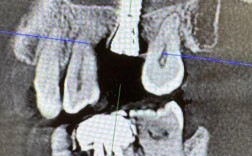

重点评估缺牙区骨量(高度、宽度、密度)、咬合关系、口腔卫生状况及余留牙健康度,可通过临床探诊测量牙槽嵴厚度,结合口腔全景片初步判断骨量,但更精准的评估需依赖影像学检查。

影像学检查

锥形束CT(CBCT)是核心工具,可三维重建颌骨结构,精确测量骨皮质厚度、骨小梁数量及方向,评估骨密度(通过灰度值转换),若CBCT显示骨量严重不足(如下颌牙槽嵴高度<8mm、上颌窦底骨量<4mm),需联合骨增量手术。